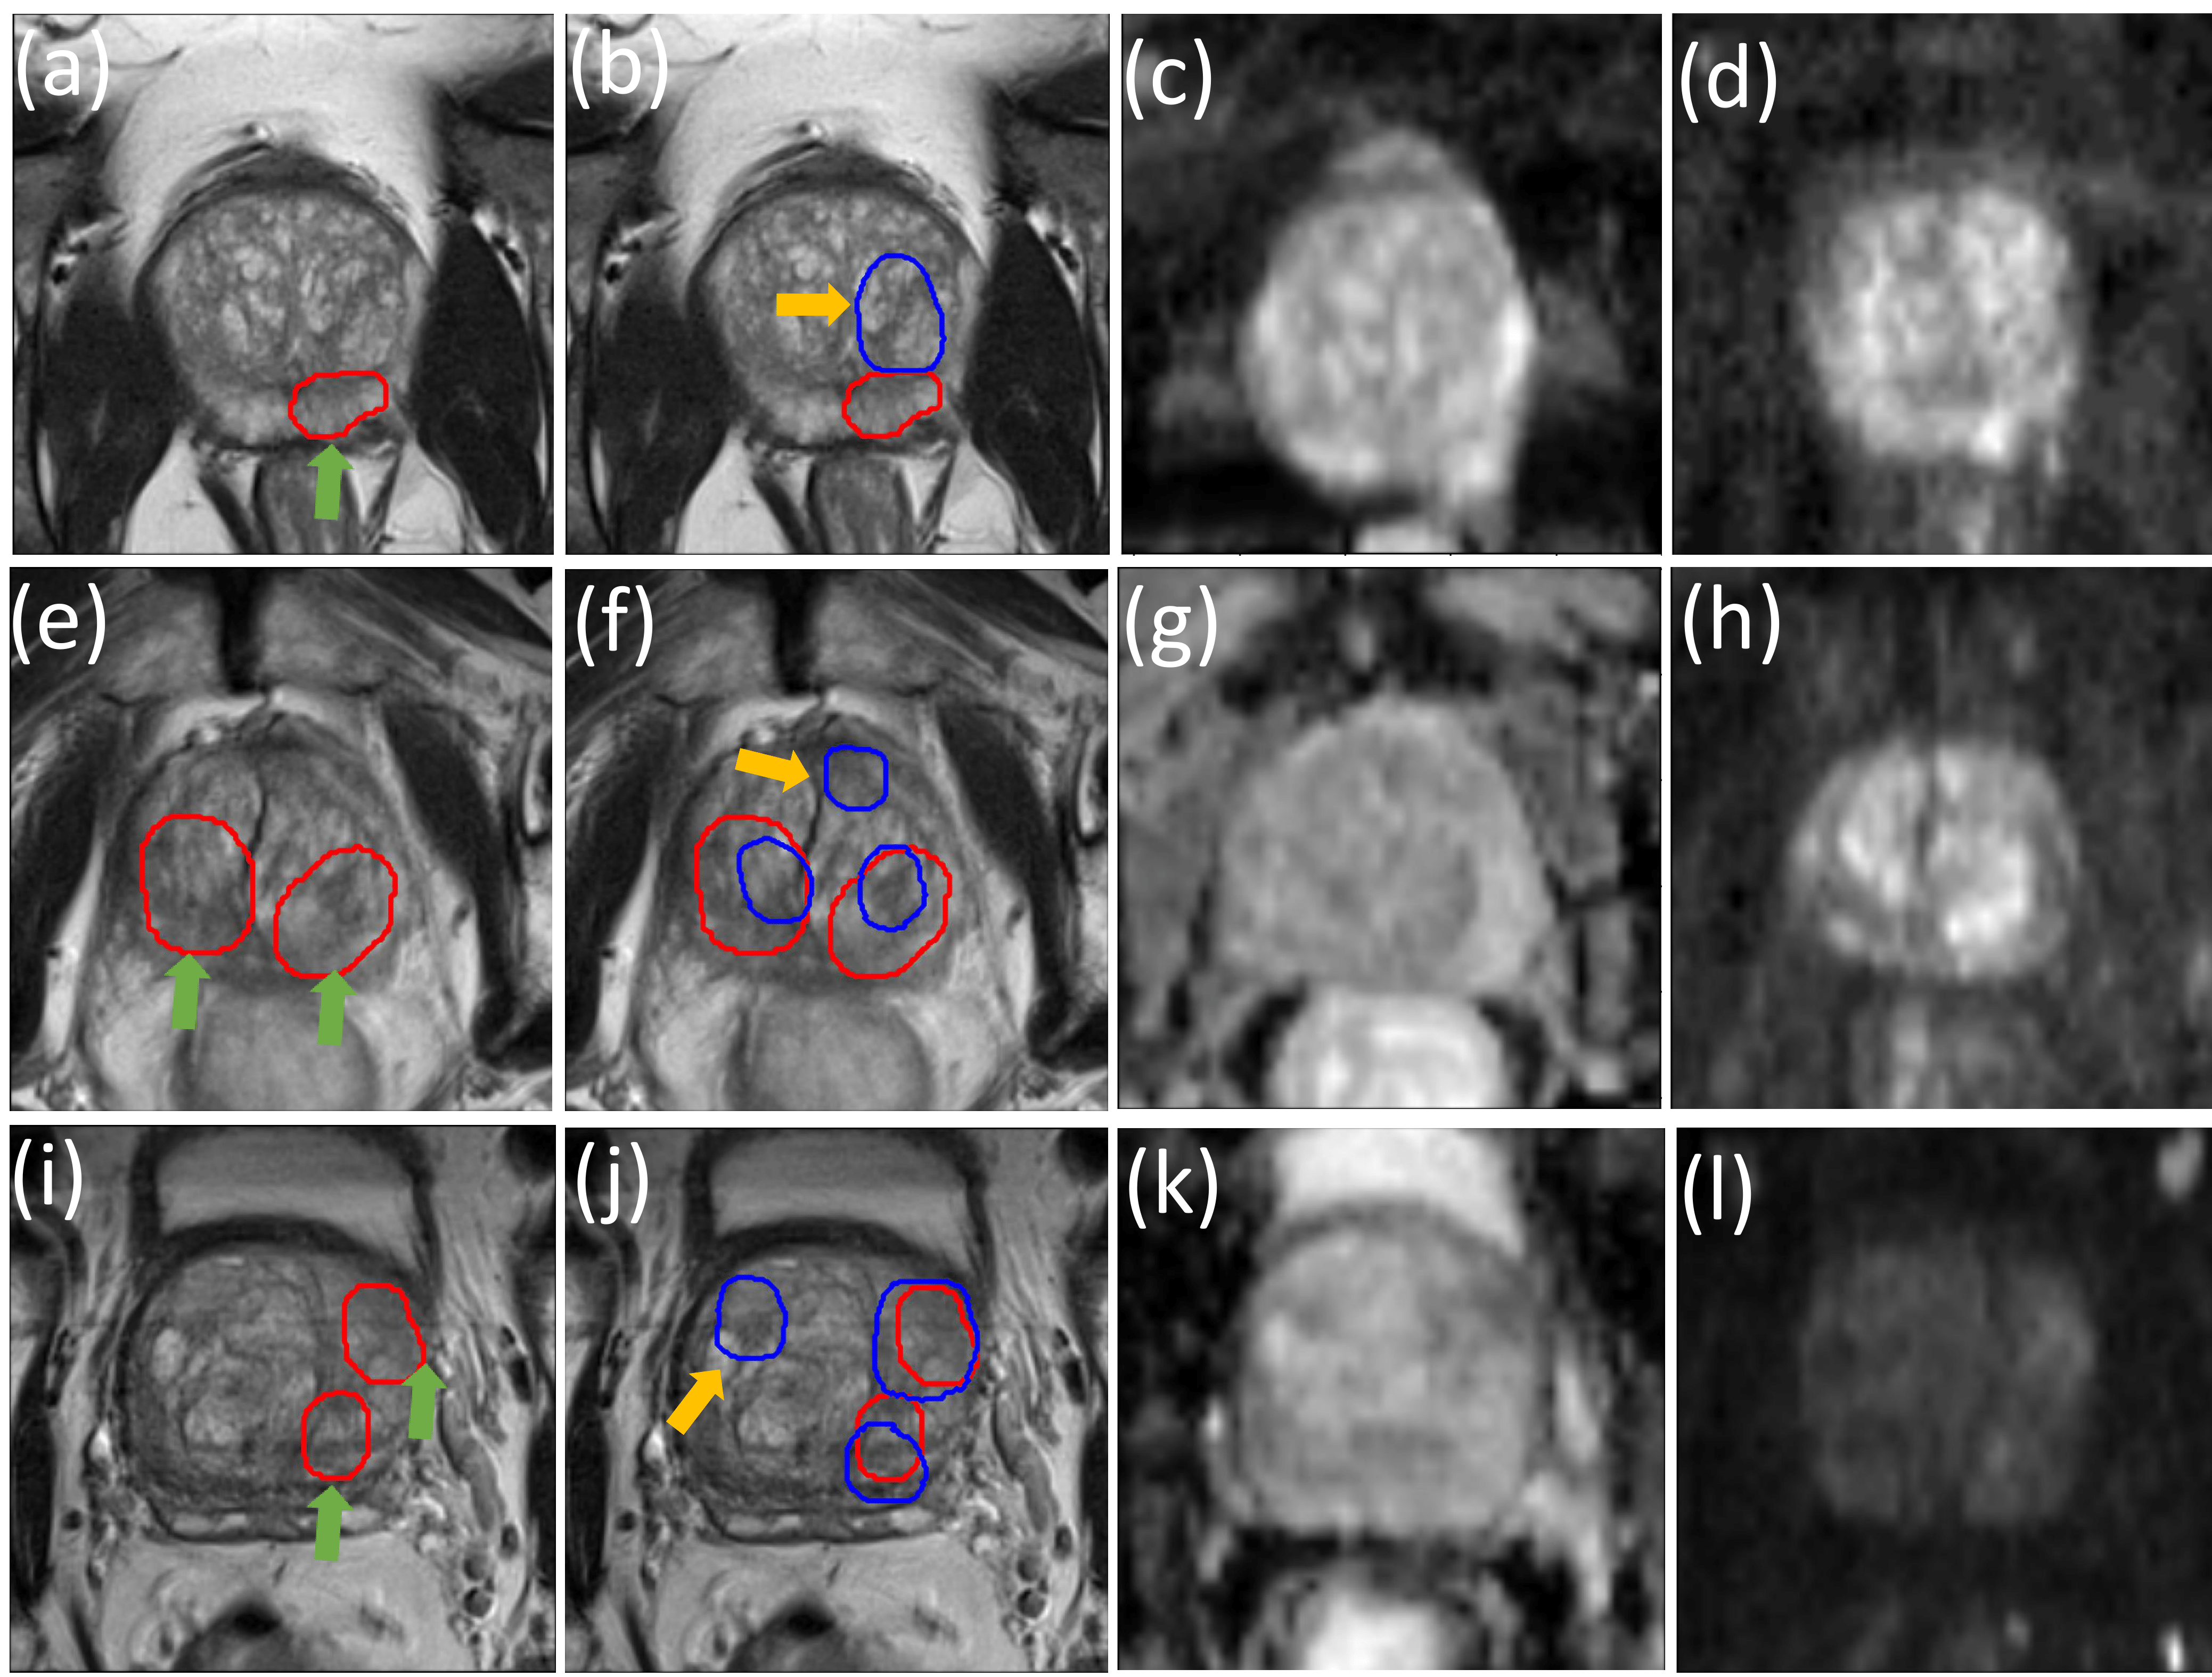

Figure 4: This figure demonstrates that both the lesion-level and slice-level FNs were reduced by incorporating Lslice_clssubscript𝐿𝑠𝑙𝑖𝑐𝑒_𝑐𝑙𝑠L_{slice\_cls} into the training process. In all the ablation examples presented in this figure, threshold=0.95threshold0.95\textsf{threshold}=0.95. Example sub-figures shown here in the same row correspond to the same slice in the test data set. (a,e,i) depicts the detection results with only the lesion-level classification loss Lcost_clssubscript𝐿𝑐𝑜𝑠𝑡_𝑐𝑙𝑠L_{cost\_cls} incorporated, where αlesion,βlesionsubscript𝛼𝑙𝑒𝑠𝑖𝑜𝑛subscript𝛽𝑙𝑒𝑠𝑖𝑜𝑛\alpha_{lesion},\beta_{lesion} vary. (b,f,j) depicts the detection results with both Lcost_clssubscript𝐿𝑐𝑜𝑠𝑡_𝑐𝑙𝑠L_{cost\_cls} and Lslice_clssubscript𝐿𝑠𝑙𝑖𝑐𝑒_𝑐𝑙𝑠L_{slice\_cls} utilized in the training. The weighting schemes in this ablation study are as follows. (a) αlesion=1,βlesion=1formulae-sequencesubscript𝛼𝑙𝑒𝑠𝑖𝑜𝑛1subscript𝛽𝑙𝑒𝑠𝑖𝑜𝑛1\alpha_{lesion}=1,\beta_{lesion}=1; (b) α=1,β=1formulae-sequence𝛼1𝛽1\alpha=1,\beta=1; (e) αlesion=1,βlesion=3formulae-sequencesubscript𝛼𝑙𝑒𝑠𝑖𝑜𝑛1subscript𝛽𝑙𝑒𝑠𝑖𝑜𝑛3\alpha_{lesion}=1,\beta_{lesion}=3; (f) α=1,β=3formulae-sequence𝛼1𝛽3\alpha=1,\beta=3; (i) αlesion=3,βlesion=1formulae-sequencesubscript𝛼𝑙𝑒𝑠𝑖𝑜𝑛3subscript𝛽𝑙𝑒𝑠𝑖𝑜𝑛1\alpha_{lesion}=3,\beta_{lesion}=1; (j) α=3,β=1formulae-sequence𝛼3𝛽1\alpha=3,\beta=1. (c,g,k) ADC images; (d,h,l) DWI b-2000 images.

Fig. 4 includes the three ablation examples where the slice-level FNs were reduced by incorporating the slice-level classification loss Lslice_clssubscript𝐿𝑠𝑙𝑖𝑐𝑒_𝑐𝑙𝑠L_{slice\_cls} into training. Three different slices are utilized to demonstrate the improvements in the three different rows in Fig. 4. Comparing Fig. 4 (b) with Fig. 4 (a), shows that the slice-level FN was reduced with the sacrifice of one more lesion-level FP. By comparing Fig. 4 (f) with Fig. 4 (e), we find that both lesion-level and slice-level FNs were reduced with one more lesion level FP. By comparing Fig. 4 (j) with Fig. 4 (i), we find that both lesion-level and slice-level FNs were reduced with the sacrifice of one more lesion-level FP.